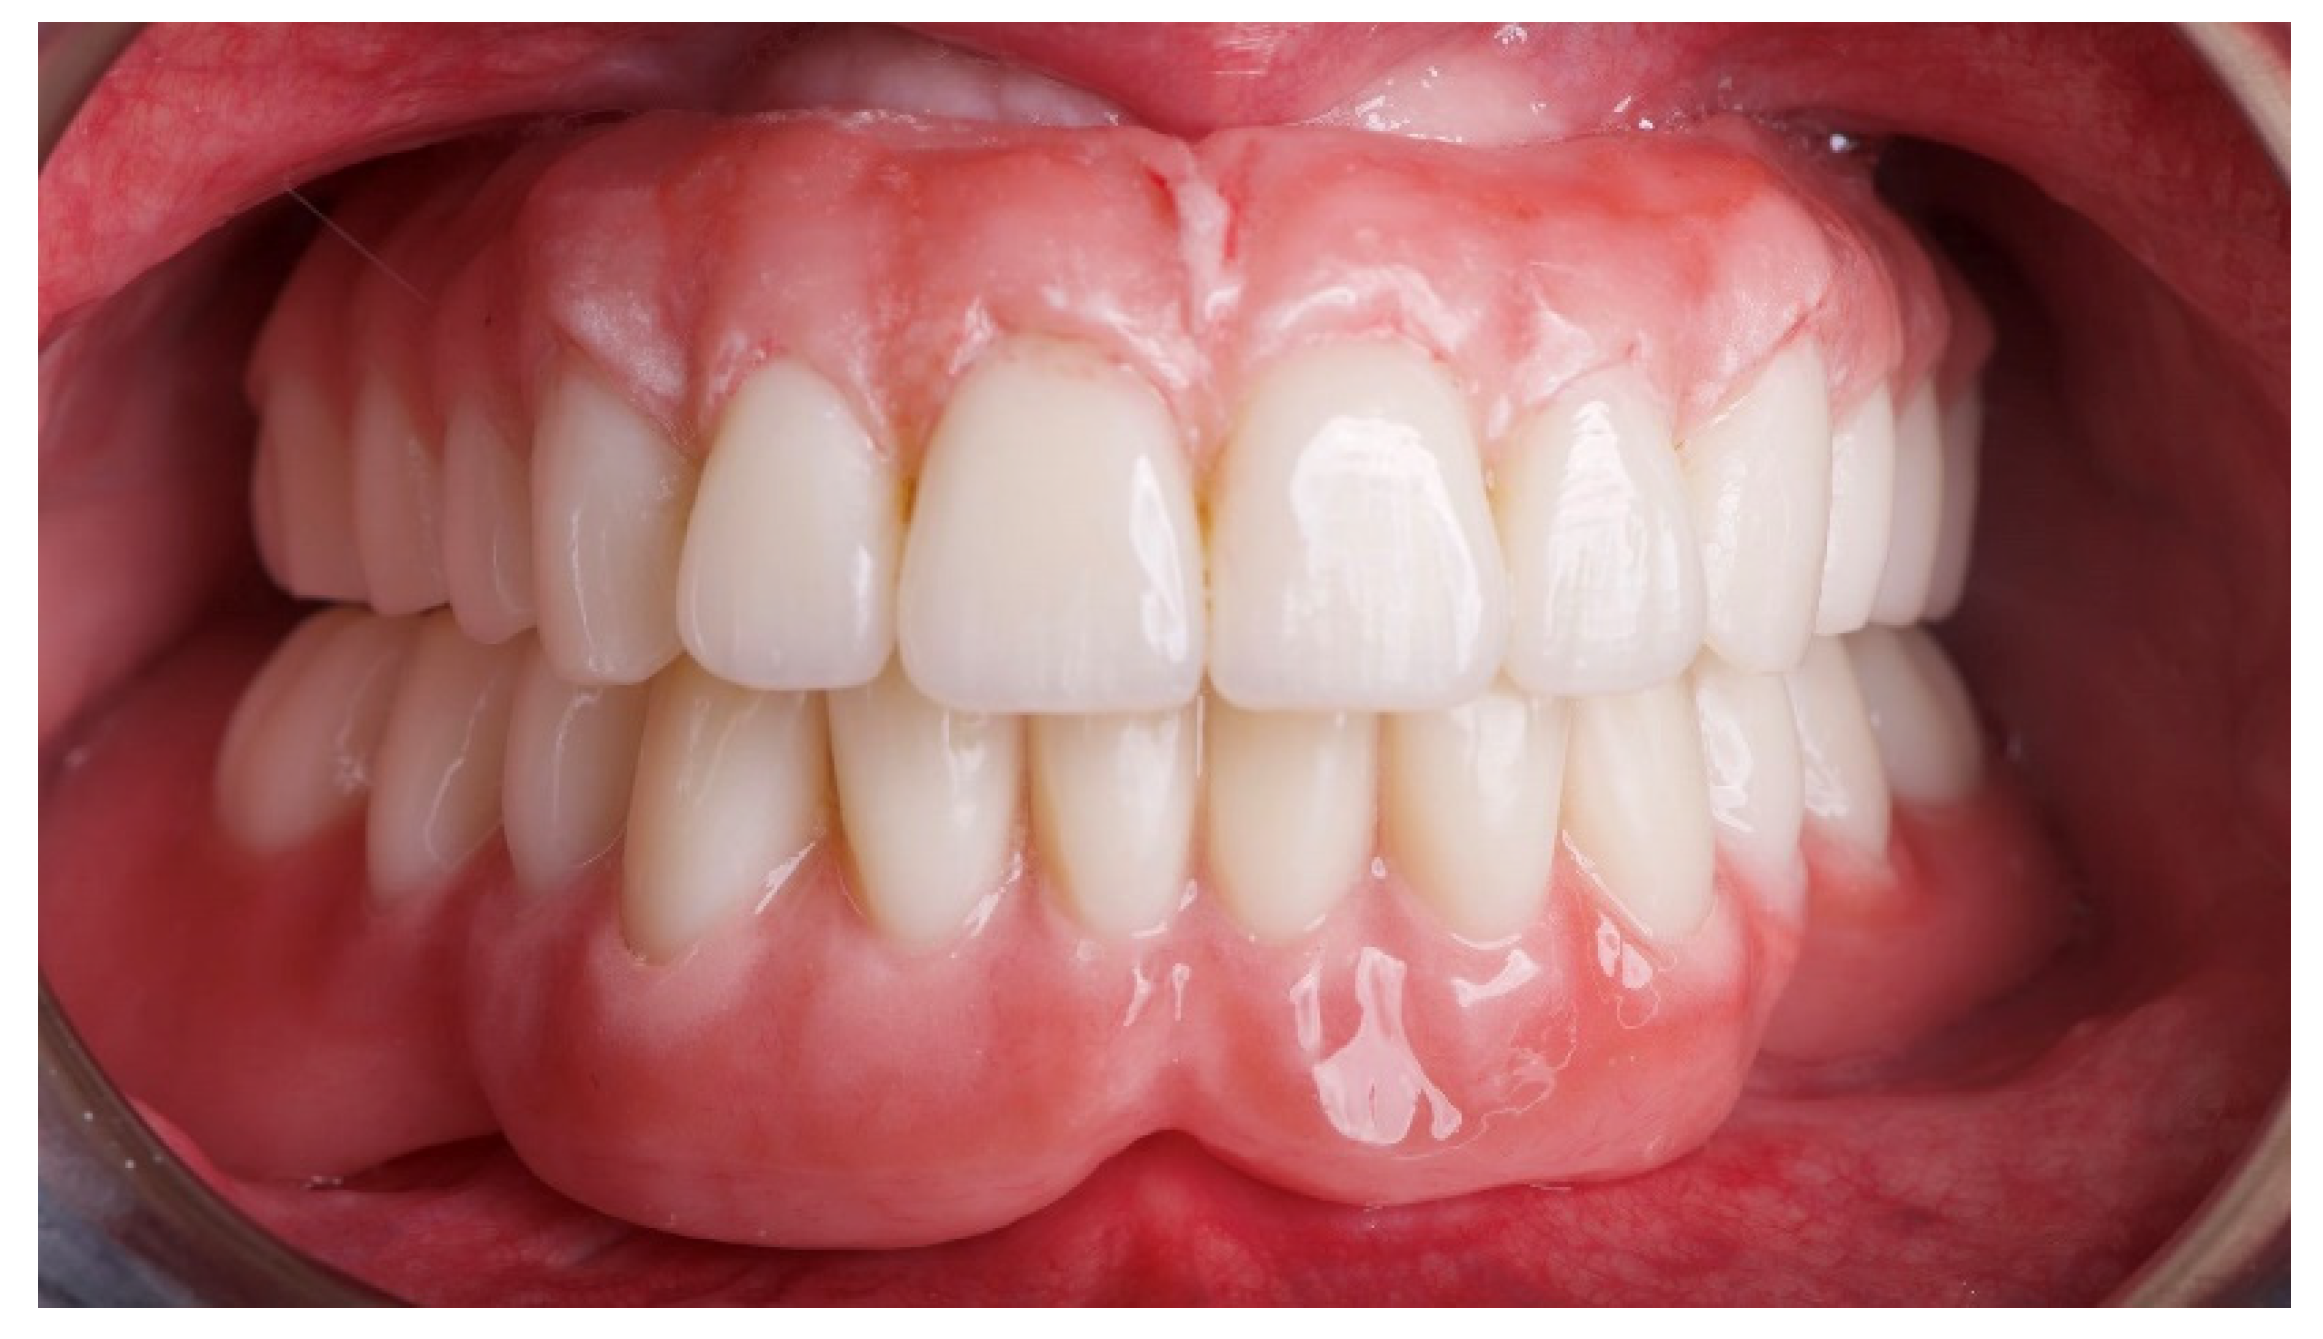

- Patients’ satisfaction was measured by means of a questionnaire delivered four months after prosthesis delivery by an independent outcome assessor. The following questions were asked: Are you satisfied with the function of your implant-supported prosthesis?; Are you satisfied with the aesthetic outcome of your implant supported prosthesis?; Would you undergo the same therapy again? Possible answers: yes absolutely; yes partly; not sure; not really; absolutely not. An operator not previously involved in the treatment of the patient filled out the questionnaire.